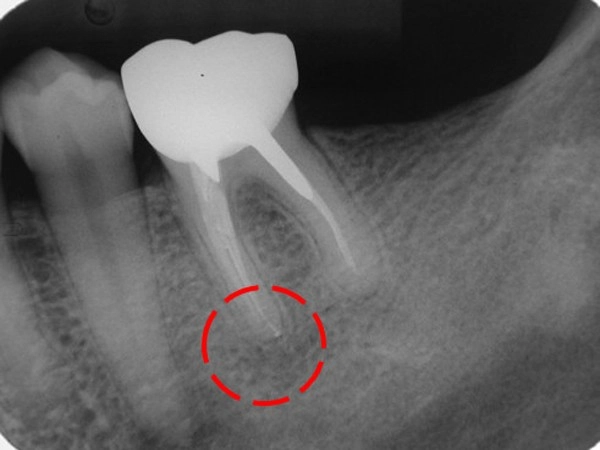

顯微根管再治療-根尖發炎案例

顯微根管-根尖區病變案例